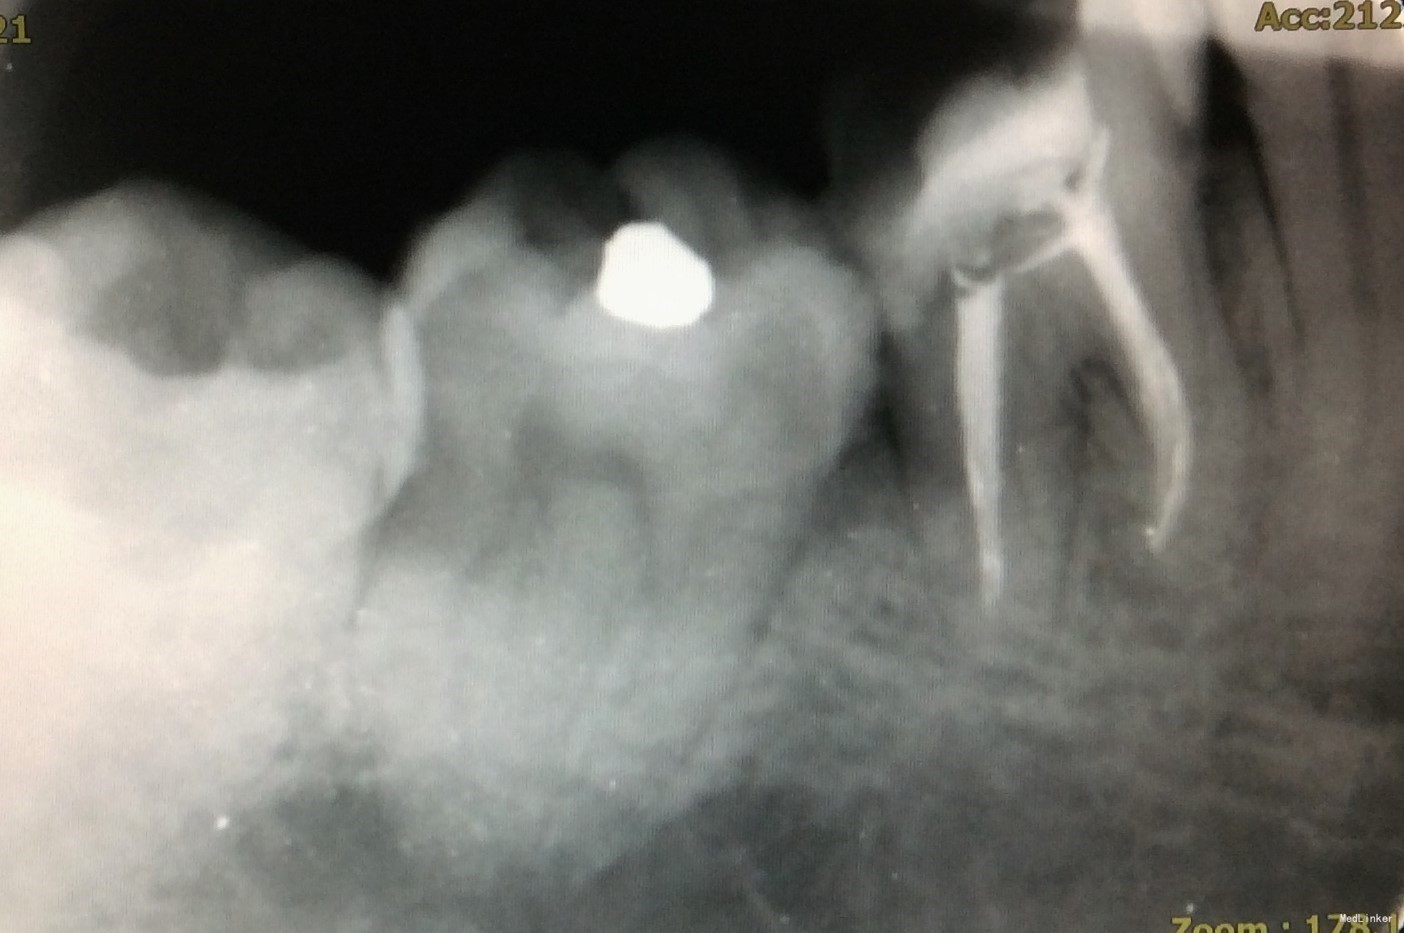

二次复诊:46牙上橡皮障,去暂封,荡洗根管,次氯酸钠冲洗,干燥根管,AH糊剂加大椎度牙胶充填根尖段根管,热牙胶封闭上段根管;远中根预备纤维桩道,粘接纤维桩,行牙体树脂粘接修复。建议观察1周,若无明显不适,至修复可行冠修复。建议牙周科会诊46牙。

2、根管预备应注意根尖孔大小。下颌磨牙通常远中根根尖孔较近中根根尖孔直径更大,行预备时应注意用K锉试探根尖孔预备是否恰当。

3、AH糊剂调拌的状态可能会影响根充的质量。本病例中,近中根、远中根均有不均匀高密度影,为相对较稠的AH糊剂。根充时应注意AH糊剂是否已固化,且应在根管中上下提拉主牙胶尖数次以使糊剂充分到达根尖处,且均匀分布于根管内。

5、从该病例中可发现,远中根根尖孔开口应位于远中,不在根尖。因根尖孔的解剖位置差异大,根管治疗应充分利用根测仪测量准确的长度,不能仅凭X线片来判断。